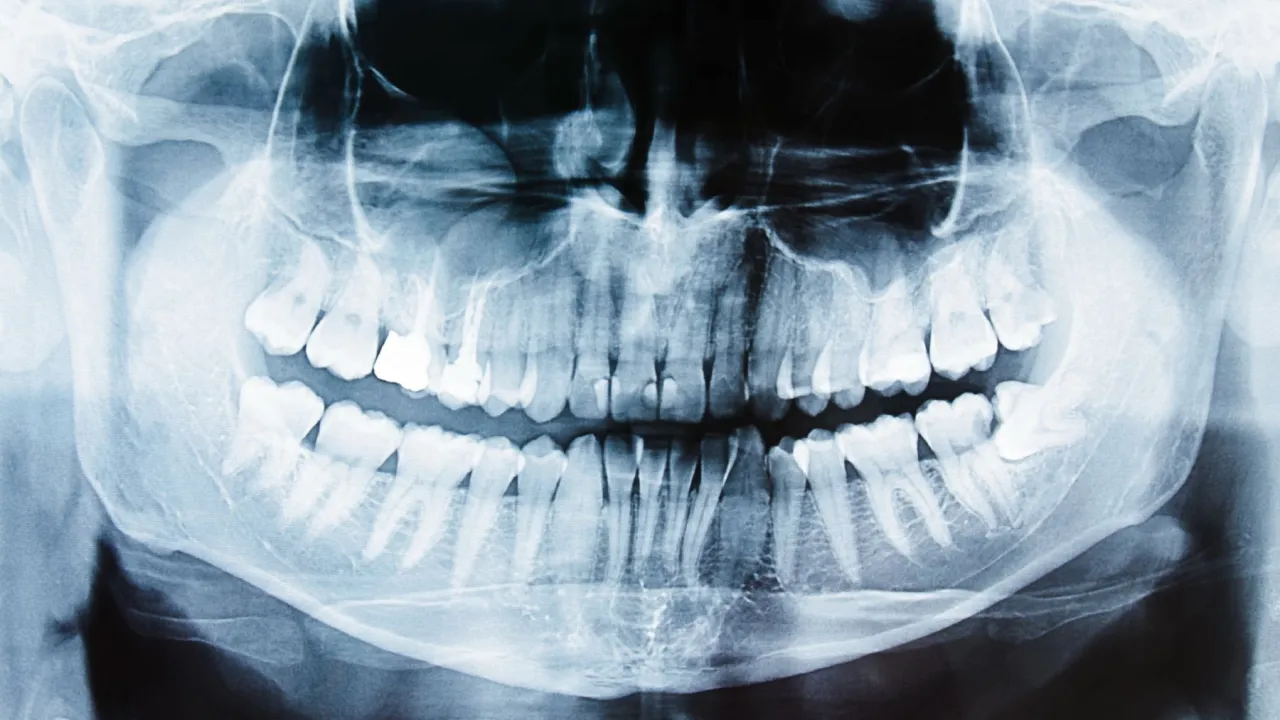

- Zmiany widoczne na zdjęciu RTG charakterystyczna "ciemna plama" wokół wierzchołka korzenia.

Niewidoczne dla oka, kluczowe dla diagnozy: Co pokaże zdjęcie RTG?

Ciemna plama wokół korzenia: Jak dentysta interpretuje obraz rentgenowski?

Wiele problemów z zębami, zwłaszcza tych wymagających leczenia kanałowego, jest niewidocznych gołym okiem. Dlatego zdjęcie rentgenowskie jest absolutnie kluczowe w diagnostyce. Na takim zdjęciu dentysta może dostrzec zmiany zapalne w kości wokół wierzchołka korzenia zęba, często określane jako "ciemna plama". Ta ciemna plama to obszar, w którym kość została zniszczona przez proces zapalny. Jej obecność jest jednoznacznym wskazaniem do leczenia kanałowego, ponieważ świadczy o zaawansowanej infekcji, która wymaga usunięcia z wnętrza zęba.

Ocena stanu kanałów i korzeni: Dlaczego RTG jest niezbędne przed leczeniem?

Poza wykrywaniem zmian zapalnych, zdjęcie RTG jest niezbędne również do oceny ogólnego stanu zęba przed podjęciem leczenia kanałowego. Pozwala mi, jako dentyście, ocenić rozległość próchnicy, stan tkanek okołowierzchołkowych, a przede wszystkim anatomię kanałów korzeniowych. Każdy ząb jest inny, a kanały mogą być proste, zakrzywione, wąskie lub rozgałęzione. Bez precyzyjnego obrazu rentgenowskiego niemożliwe byłoby zaplanowanie skutecznego i precyzyjnego leczenia. To właśnie dzięki RTG mogę dokładnie zobaczyć, z czym mam do czynienia i jak najlepiej przeprowadzić zabieg.